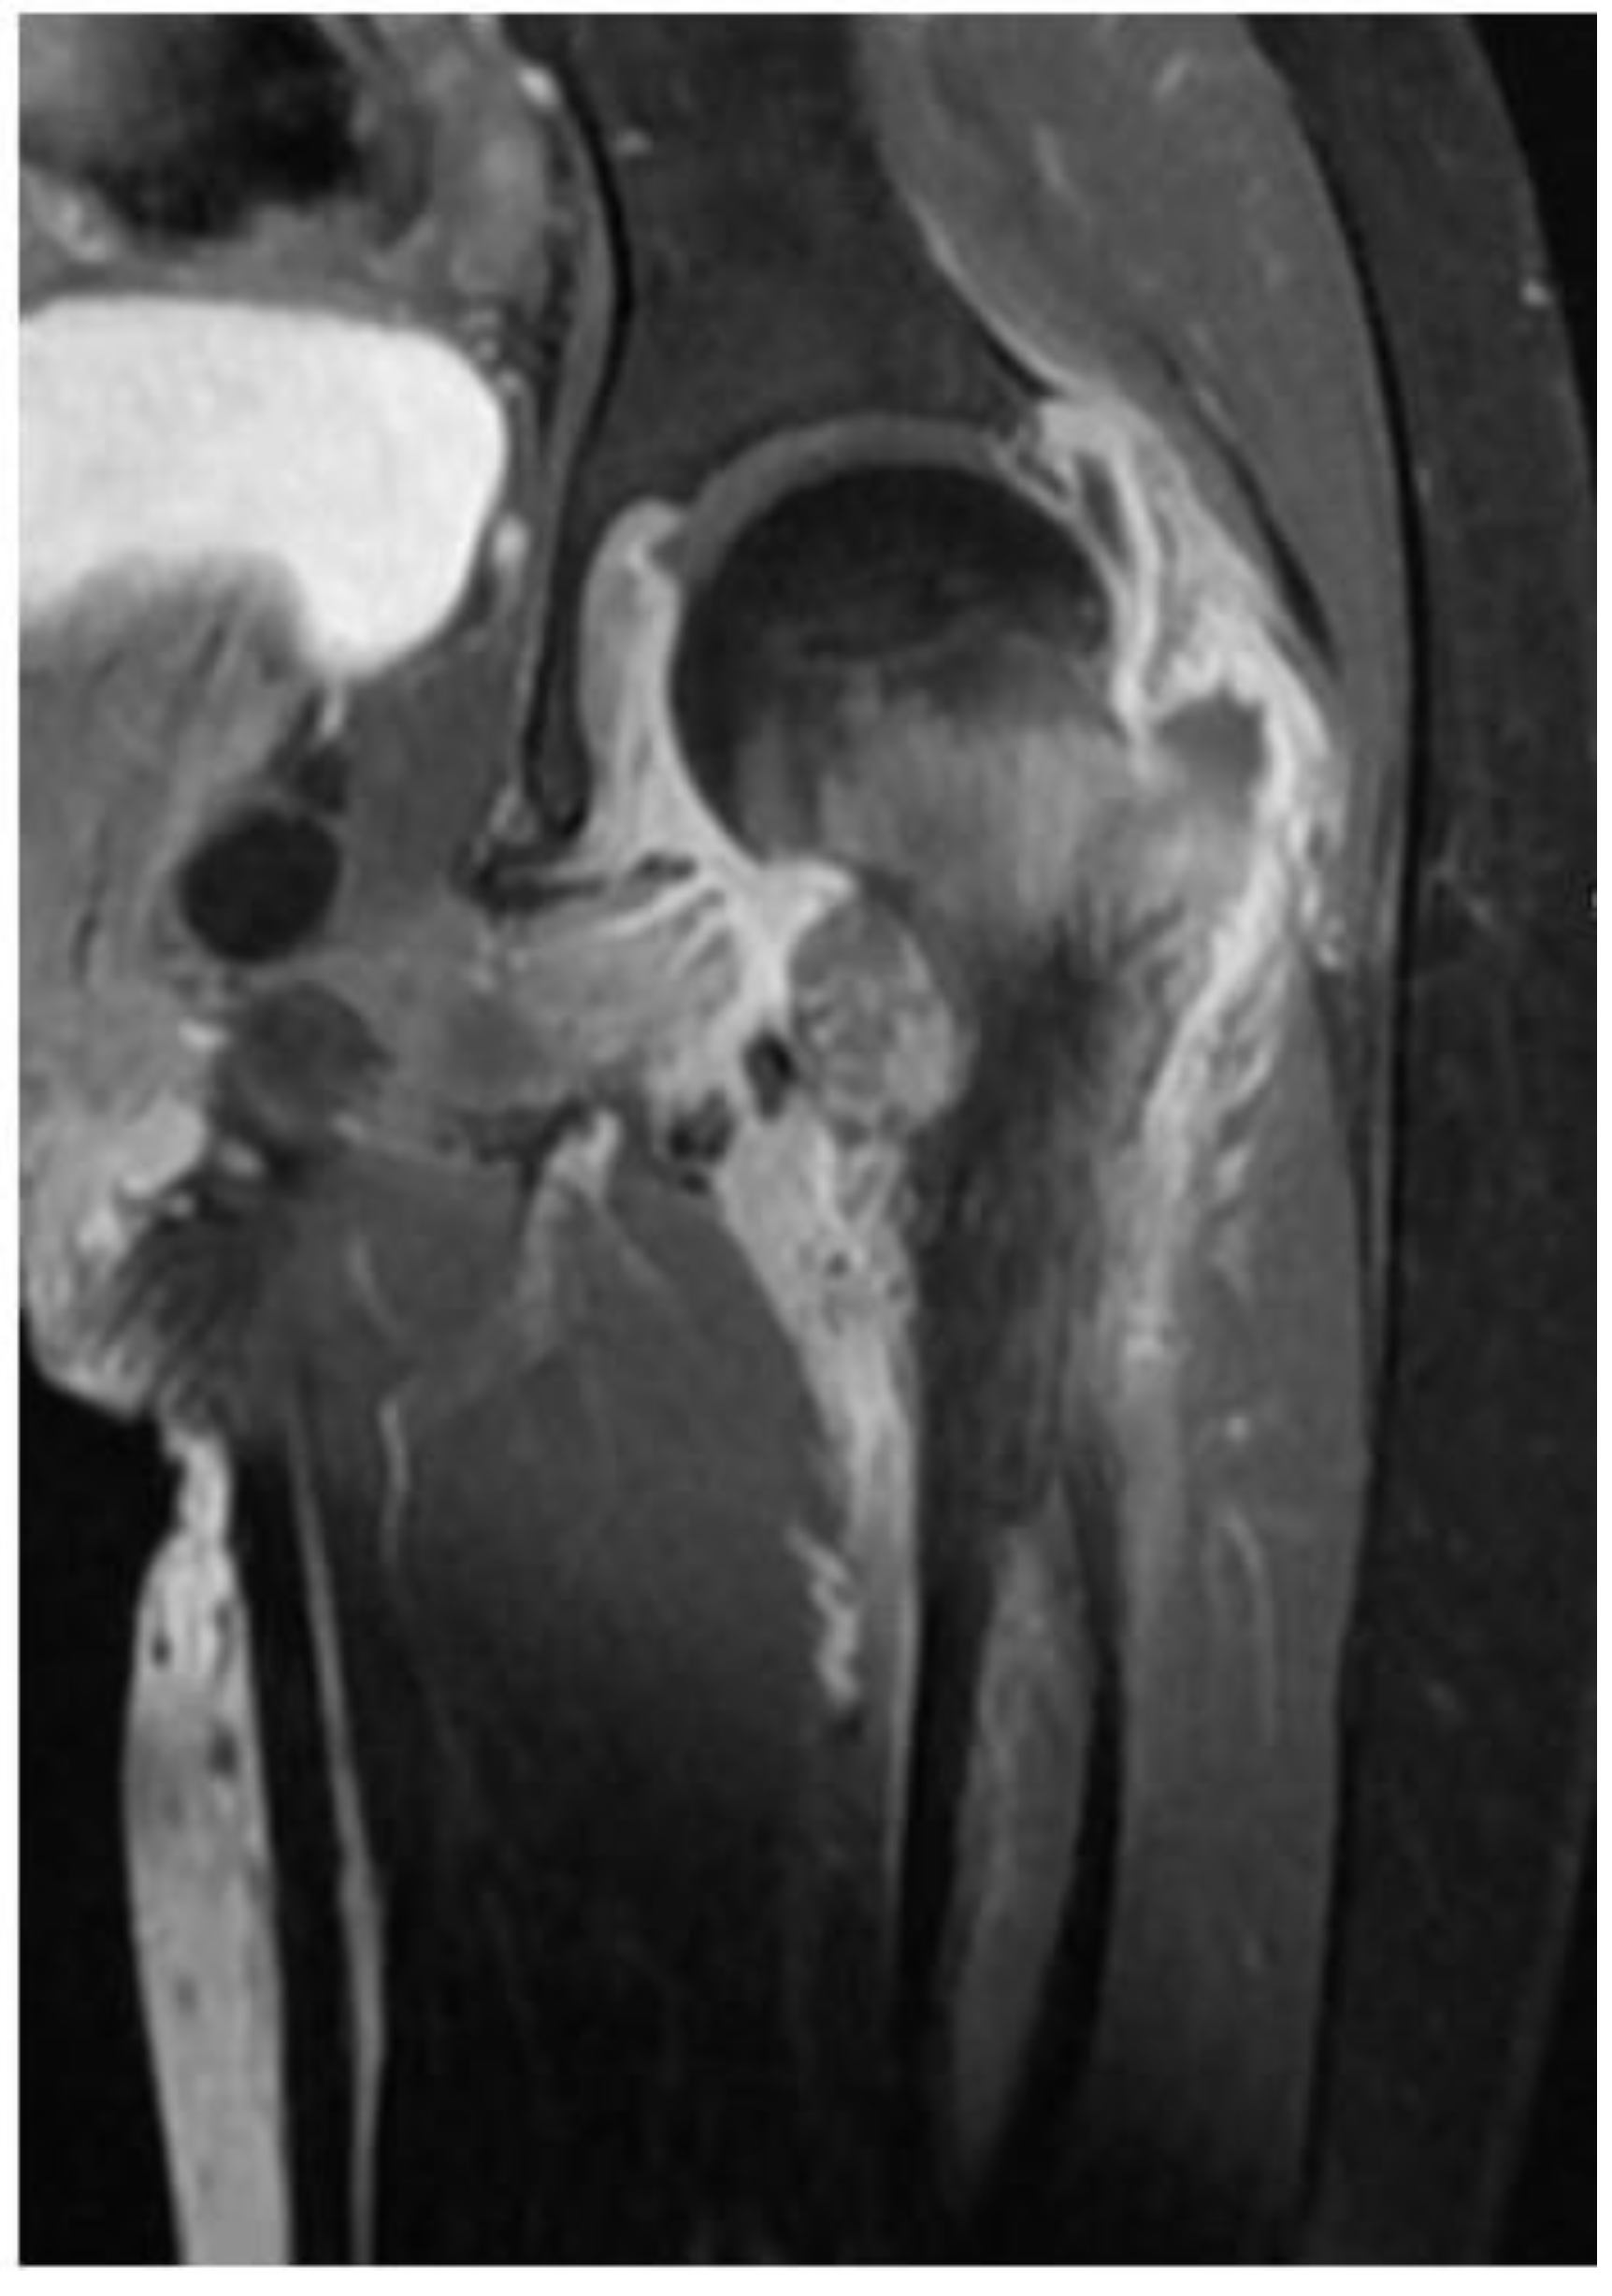

The patient was referred to the rheumatology service for further evaluation. Given the initial CT findings, Magnetic Resonance Imaging (MRI) of the hip was obtained, which showed evidence of chronic arthritis (Figure 2). Therefore, she was started on non-steroidal anti-inflammatory drug (NSAID) and given a working diagnosis of juvenile idiopathic arthritis (JIA).

Figure 2.

Magnetic Resonance Imaging (MRI) of the hip revealed bony overgrowth of the lesser trochanter with early cystic formation and a fluid-fluid level, extensive bone marrow edema, extensive adjacent soft tissue edema and hip joint effusion with evidence of synovial thickening and enhancement post contrast administration.